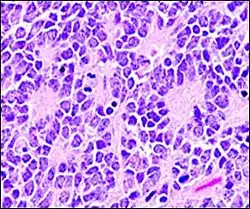

Micrograph of perivascular pseudorosettes Micrograph of perivascular pseudorosettes

A perivascular pseudorosette consists of a spoke-wheel arrangement of cells with tapered cellular processes radiates around a wall of a centrally placed vessel. The modifier “pseudo” differentiates this pattern from the Homer Wright and Flexner-Wintersteiner rosettes, perhaps because the central structure is not actually formed by the tumor itself, but instead represents a native, non-neoplastic element. Also, some early investigators argued about the definition of a central lumen, choosing “pseudo” to indicate that the hub was not a true lumen but contained structures. Nevertheless, this pattern remains extremely diagnostically useful and the modifier unnecessarily leads to confusion. Perivascular pseudorosettes are encountered in most ependymomas regardless of grade or variant. As such, they are significantly more sensitive for the diagnosis of ependymomas than true ependymal rosettes. Unfortunately, perivascular pseudorosettes are also less specific in that they are also encountered in medulloblastomas, PNETs, central neurocytomas, and less often in glioblastomas, and a rare pediatric tumor, monomorphous pilomyxoid astrocytomas.[2]